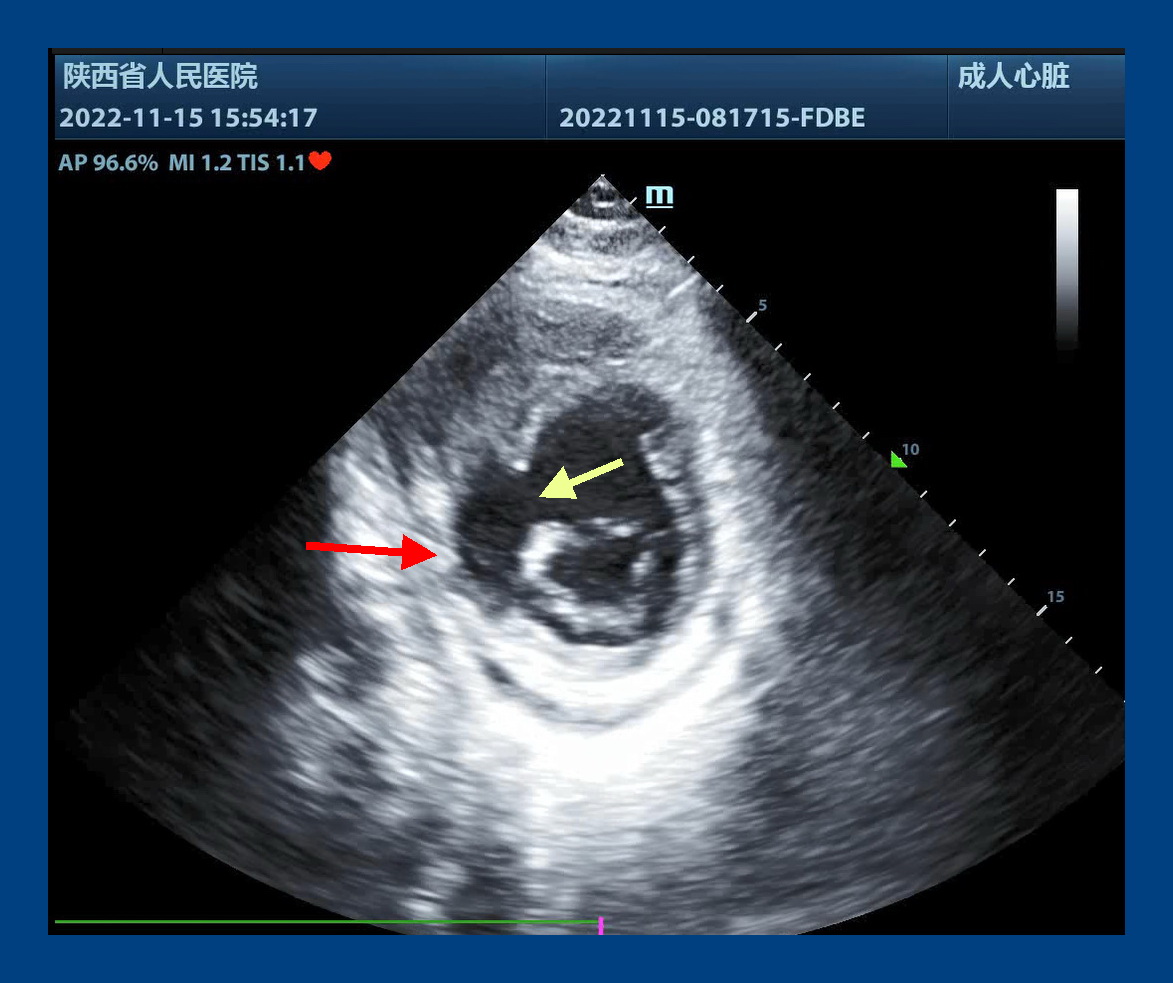

心脏外科,付建莉主任医师心脏超声检查,确诊为心脏左室下壁瘤样膨出,与正常室壁呈矛盾运动,测其瘤口为41mm,瘤深27mm,后室间隔下壁回声失落,左室面缺损口大小38mm,右室面缺损口大小21mm,病情十分危急。